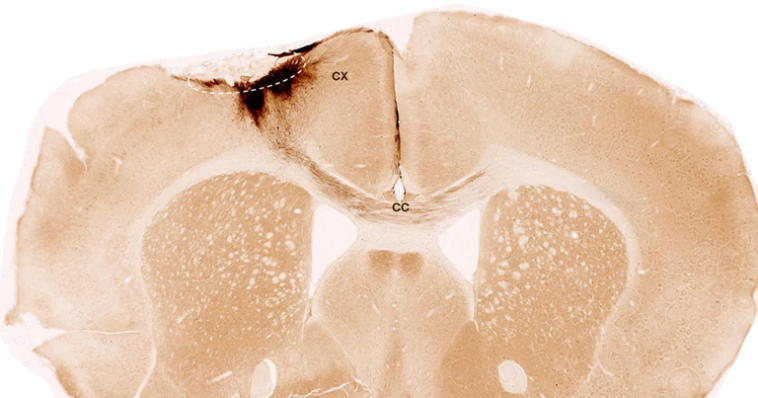

ინსულტიდან ერთი კვირის შემდეგ, მკვლევრებმა ნეირალური ღეროვანი უჯრედები ტვინის დაზიანებულ რეგიონში გადანერგეს და შემდგომი პროგრესი უახლესი ვიზუალიზაციისა და ბიოქიმიური მეთოდების გამოყენებით შეისწავლეს. შედეგებმა მეცნიერების მოლოდინს გადააჭარბა. ღეროვანი უჯრედები არა მხოლოდ ხუთი კვირის განმავლობაში გადარჩნენ, არამედ მათი უმეტესობა ნეირონებად გარდაიქმნა, რომლებმაც არსებულ ტვინის უჯრედებთან კომუნიკაციაც კი დაამყარეს.

გარდა ამისა, დაფიქსირდა რეგენერაციის დამატებითი ნიშნები: სისხლძარღვების ახალი ფორმირება, ანთებითი პროცესების შესუსტება და დაზიანებული უბნის მთლიანობის გაუმჯობესება. რაც მთავარია, ღეროვანი უჯრედების ტრანსპლანტაციამ თაგვებში ინსულტით გამოწვეული მოტორული დარღვევები მნიშვნელოვნად შეამცირა, რაც დადასტურდა ხელოვნური ინტელექტის დახმარებით ჩატარებული სიარულის ანალიზით.